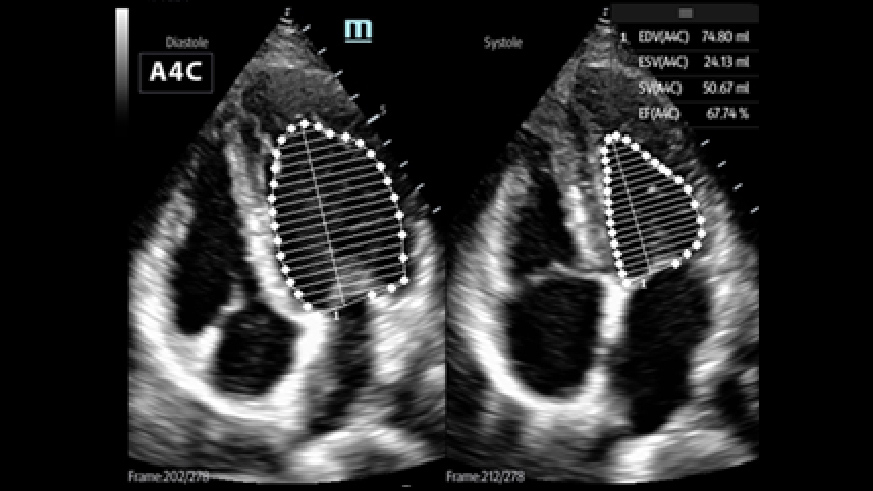

Avec des performances exceptionnelles en matiÃĻre d'imagerie cardiaque et des outils d'analyse avancÃĐs, le ME8 rÃĐpond aux besoins des soins intensifs gr?ce à une image de qualitÃĐ, une grande simplicitÃĐ dâutilisation et une extrÊme portabilitÃĐ.

Des outils intelligents pour la gestion des fluides

2Smart VTI (ITV)

Mesure automatique de lâintÃĐgrale temps Vitesse (ITV) et du dÃĐbit cardiaque pour permettre une ÃĐvaluation rapide de la fonction cardiaque. Lâoutil place automatiquement la boite couleur et la ligne de tir du doppler pulsÃĐ en temps rÃĐel. Un graphique de tendances reprÃĐsentant le dÃĐbit cardiaque, le volume dâÃĐjection systolique et lâITV aide à la prise de dÃĐcision.